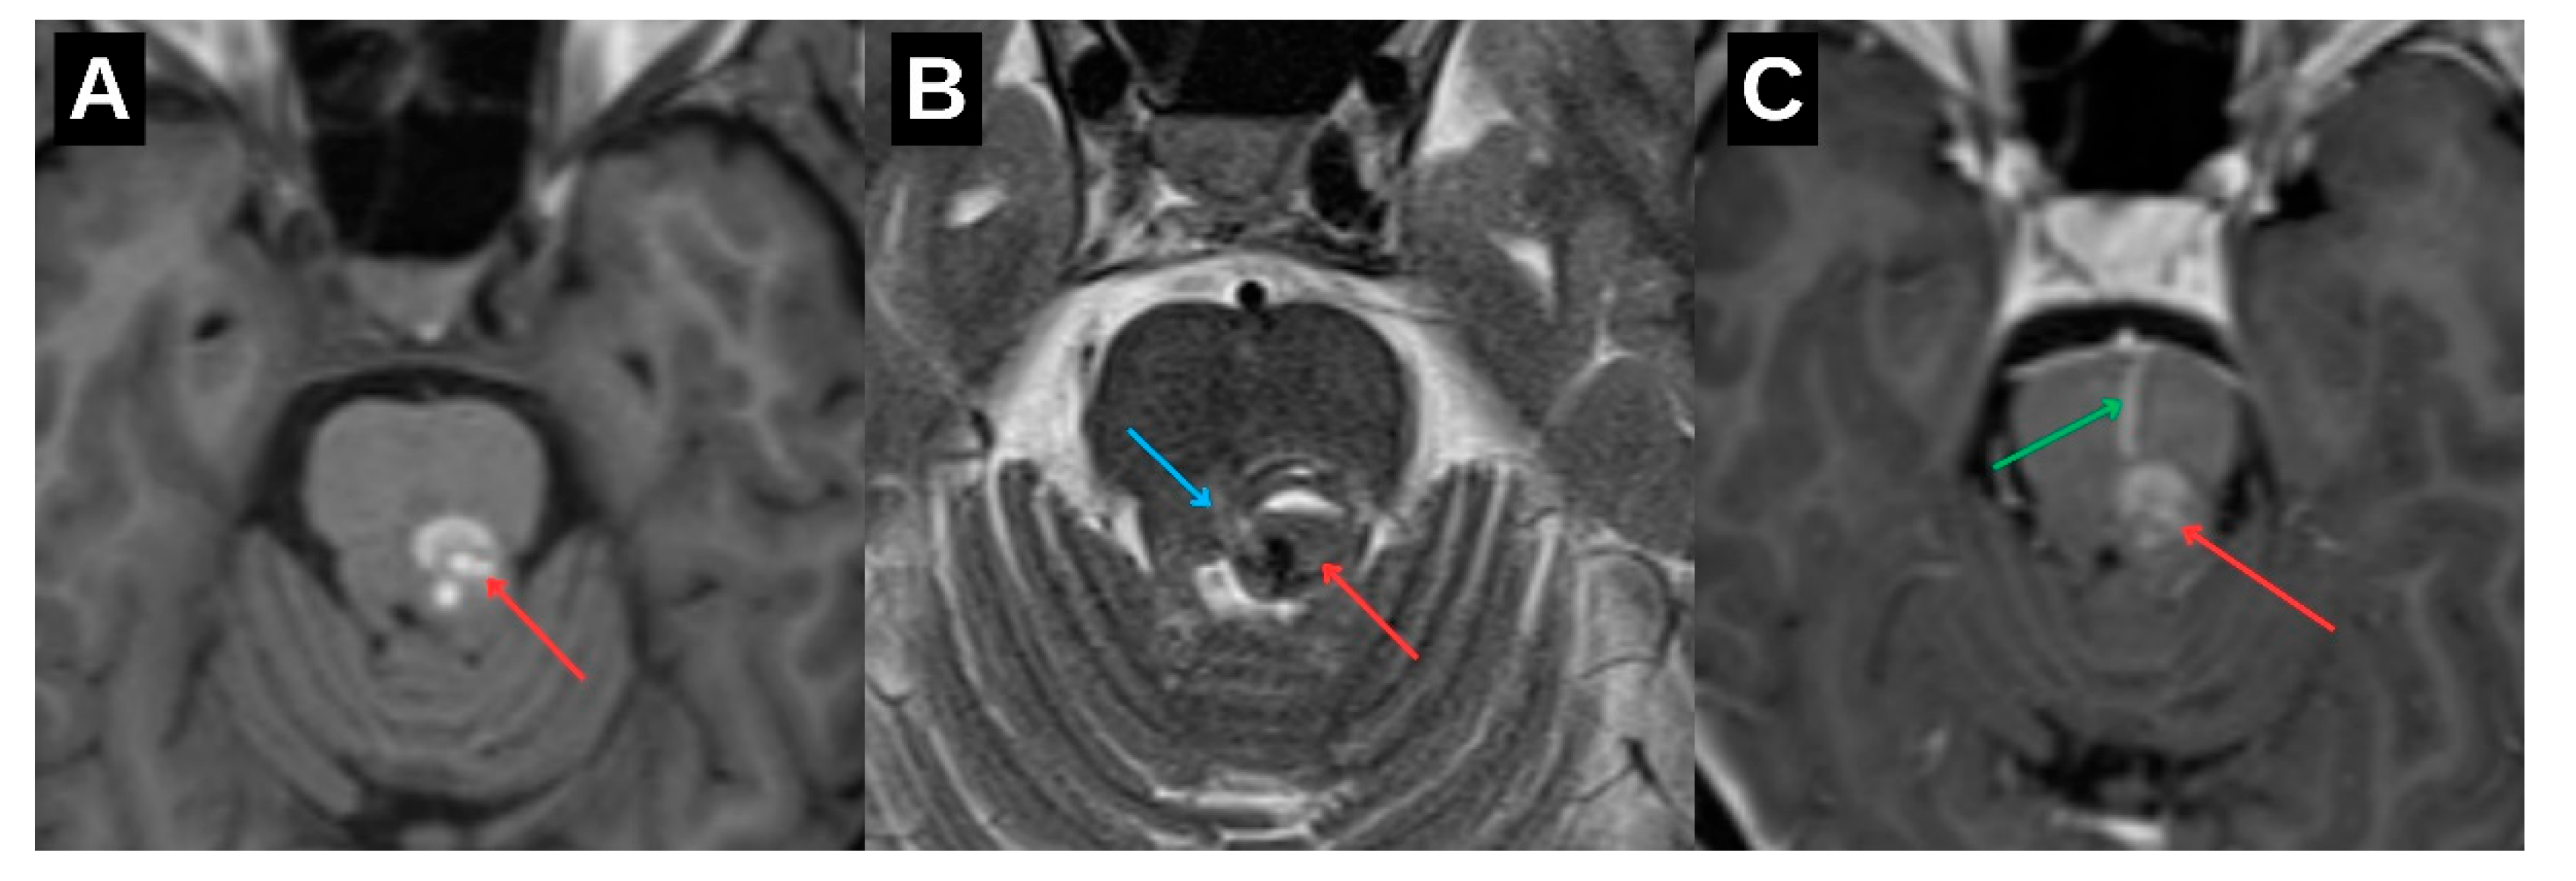

Further progression of olivary changes was noted on repeat MRI performed 1.5 years after the initial hemorrhagic event, which demonstrated continued enlargement of the inferior olivary nucleus, with the craniocaudal diameter reaching approximately 1.6 cm and anteroposterior thickness of 0.5 cm. (

Figure 4C) Signal abnormalities on T2-weighted and FLAIR sequences persisted, while no atrophy was observed. These radiological findings were consistent with Stage 2 in the traditional 3-stage classification of HOD, representing the hypertrophic phase.

Magnetic resonance imaging (MRI) remains the cornerstone of HOD diagnosis and staging. The condition demonstrates a predictable radiological progression: T2-weighted and FLAIR hyperintensity of the ION without hypertrophy in the early phase (stage 1), evolving into hypertrophy with persistent signal hyperintensity (stage 2), and eventually normalization or mild atrophy with persistent hyperintensity (stage 3). In this patient, serial MRI examinations at 6 months and again at 1.5 years post-hemorrhage demonstrated the expected imaging evolution. This case also provides a rare opportunity to illustrate the dynamic radiological progression of HOD over time, as visualized in

Figure 4. Such longitudinal documentation is uncommon in the literature, underscoring the value of systematic follow-up. Crucially, the absence of mass effect, contrast enhancement, or diffusion restriction helped exclude neoplastic, infectious, or demyelinating etiologies [